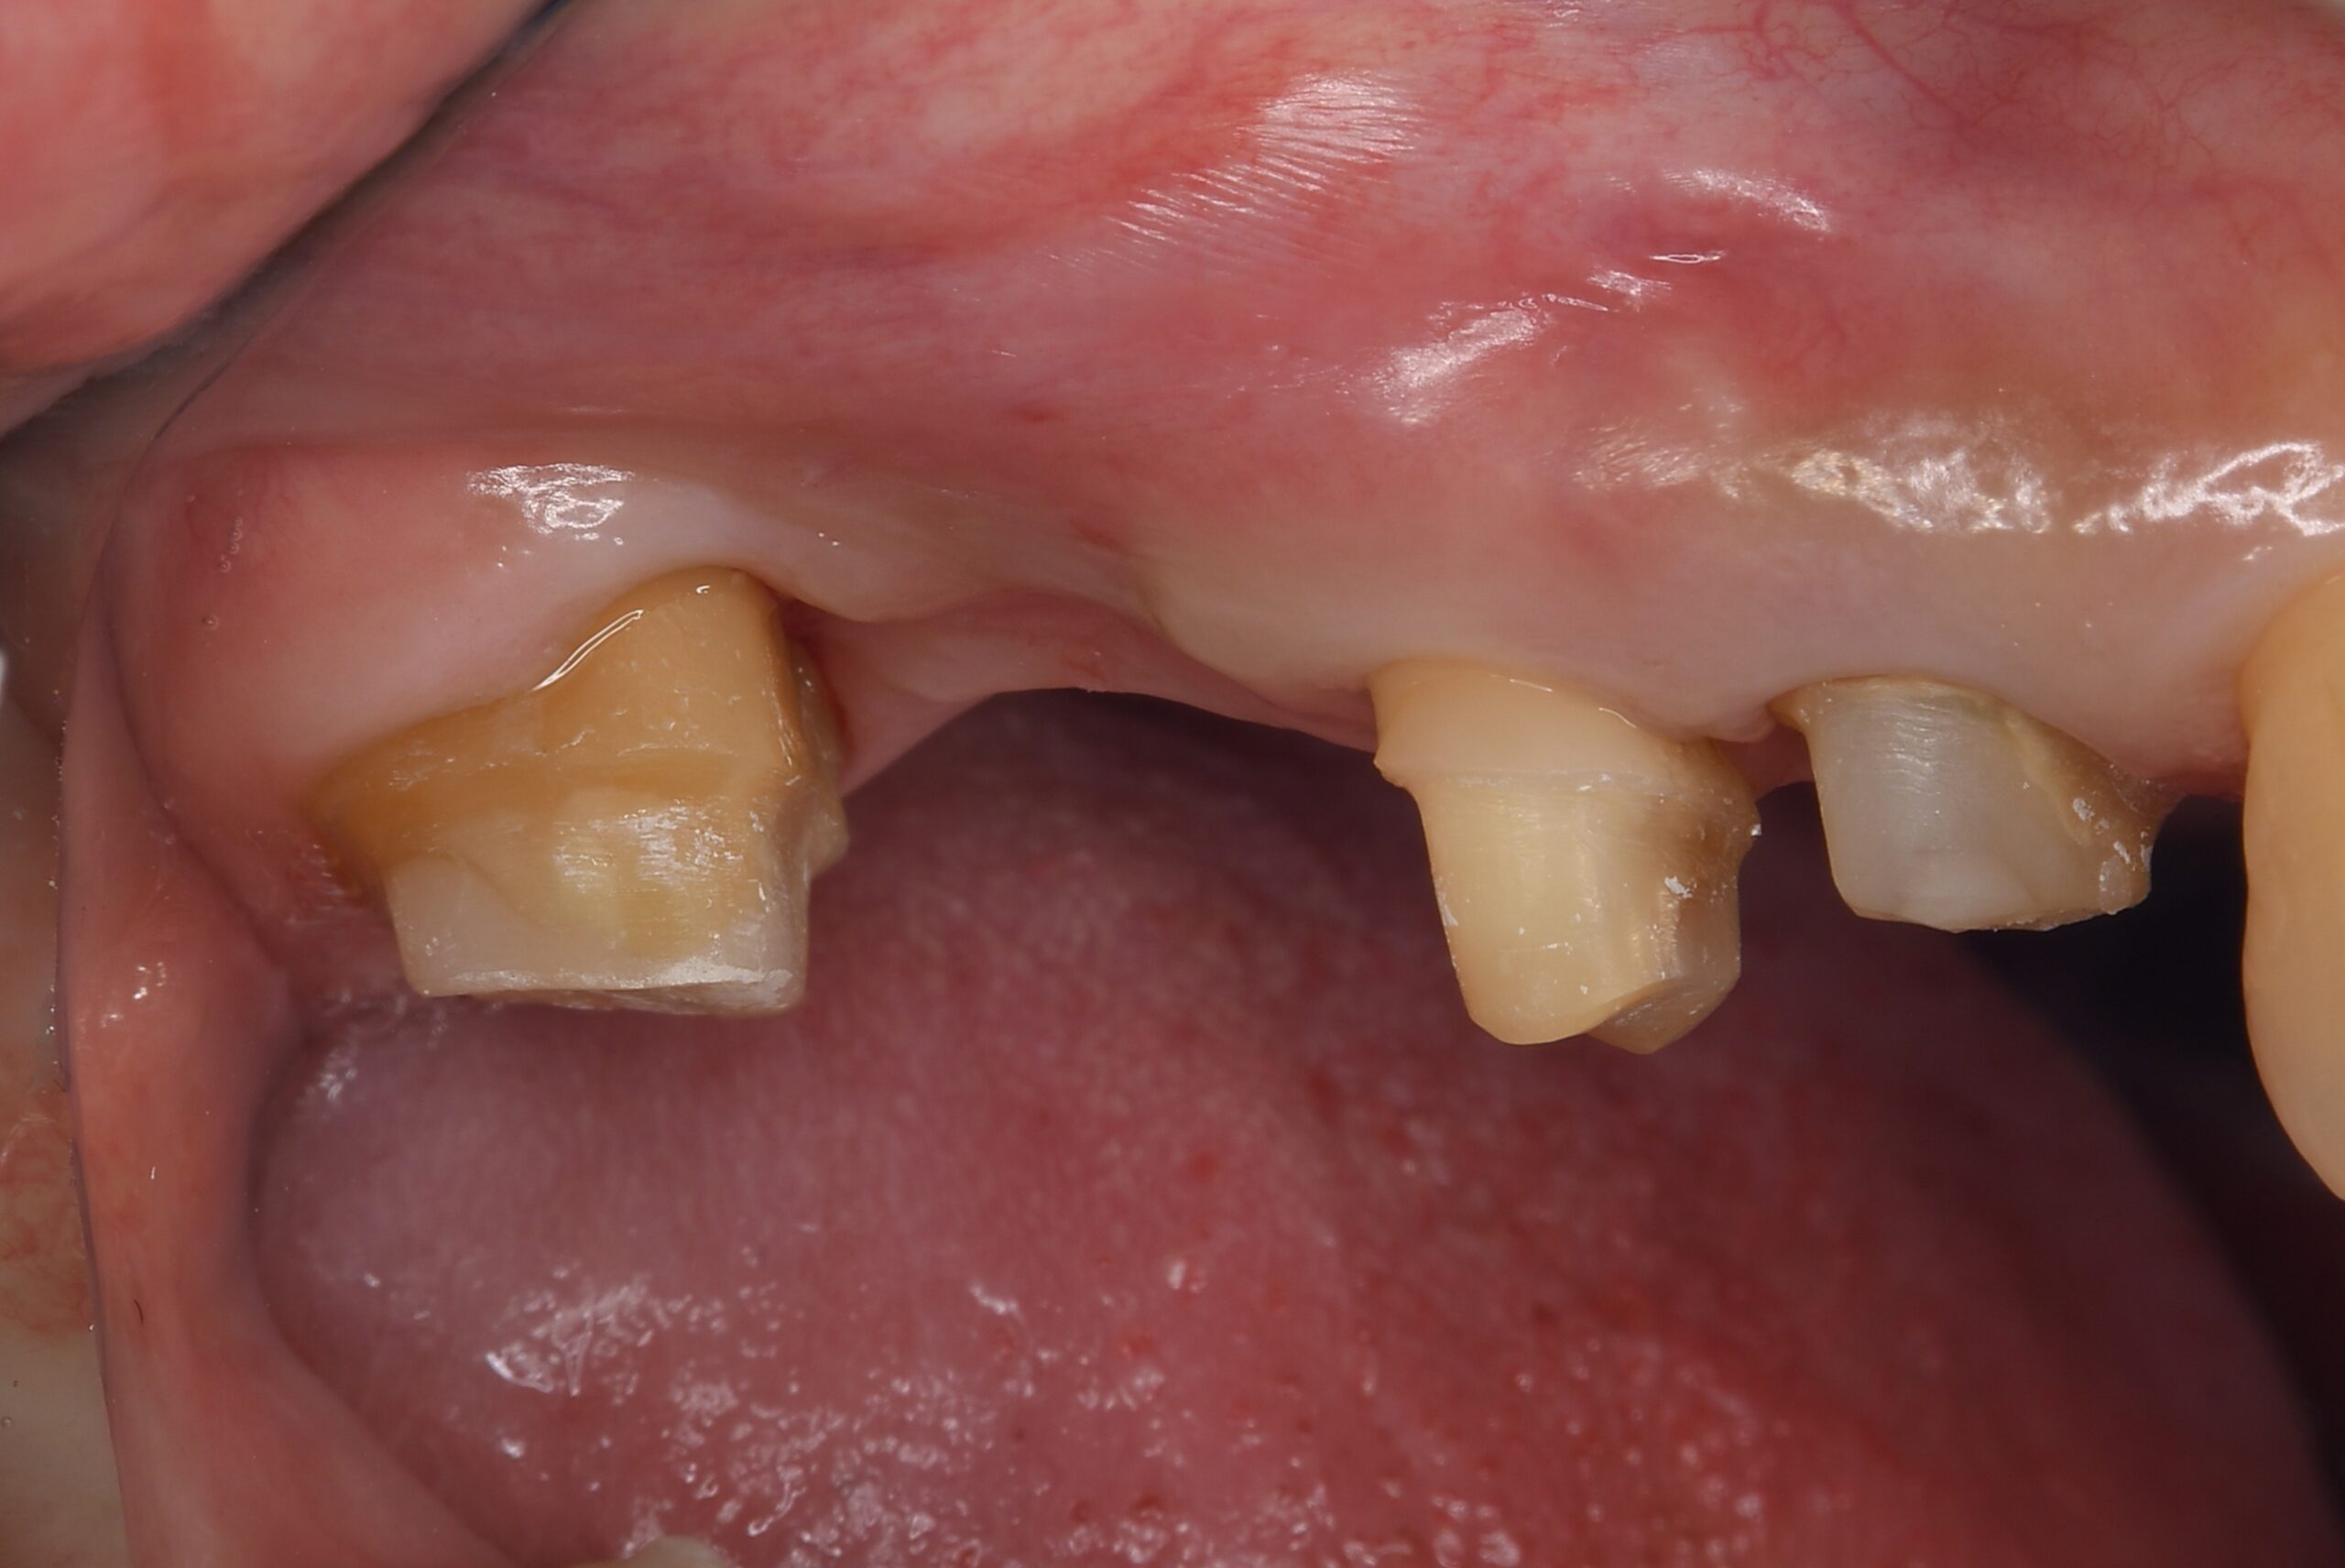

症例1:パーフォレーションリペア症例

(歯の中に大きな穴が空いてしまっているのを埋めて再生を促す治療)

歯に穴が空いていて骨に炎症がある状態 |

BEFORE |

人為的根穿孔を起こした部分に感染を起こしており、歯周ポケットが9㎜ありました。 ラバーダム防湿とマイクロスコープを使用して丁寧に治療を行いました。 殺菌性があり歯を補強することのできるMTAという根管充填材料を使用して、歯周ポケットは2㎜に改善しました。 |